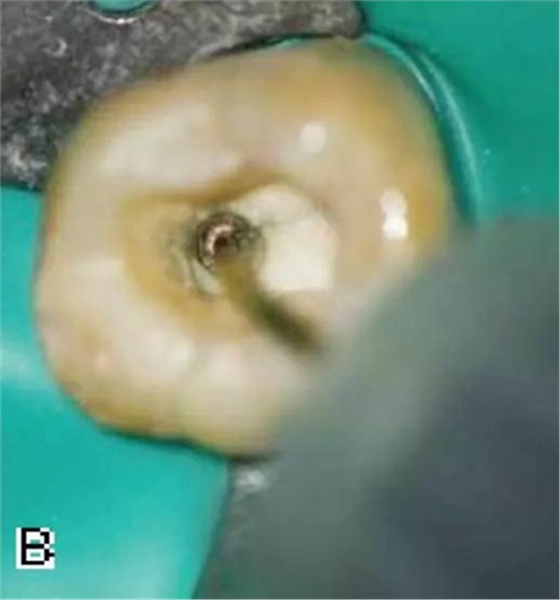

3、試尖

選擇非標(biāo)準(zhǔn)牙膠尖(如0.04、0.06 錐度牙膠尖)作為主尖,型號一般與根管預(yù)備最大號的器械型號一致,能到達(dá)距根尖0.5~1 mm 處,主尖尖段與根管壁緊密接觸。拍試尖X 線片進(jìn)行確認(rèn)(圖3)。

圖3 試尖,A.試主尖 B.拍試尖X片